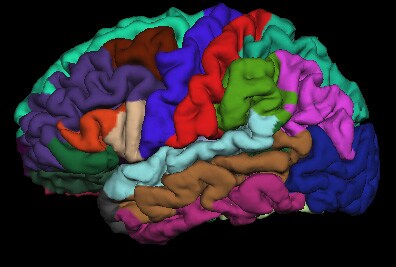

Рис 2.А.– автоматическая сегментация и рассчет объемов структур мозга по данным МРТ позволяет локализовать и оценить повреждения белого и серого вещества мозга.